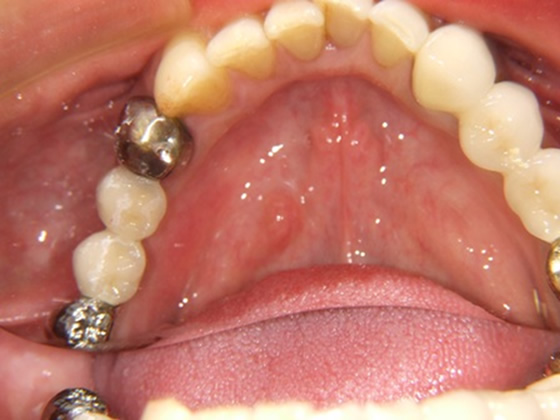

50歳代 男性 右下臼歯部 インプラント植立

セラミック冠を装着したところ(上から)